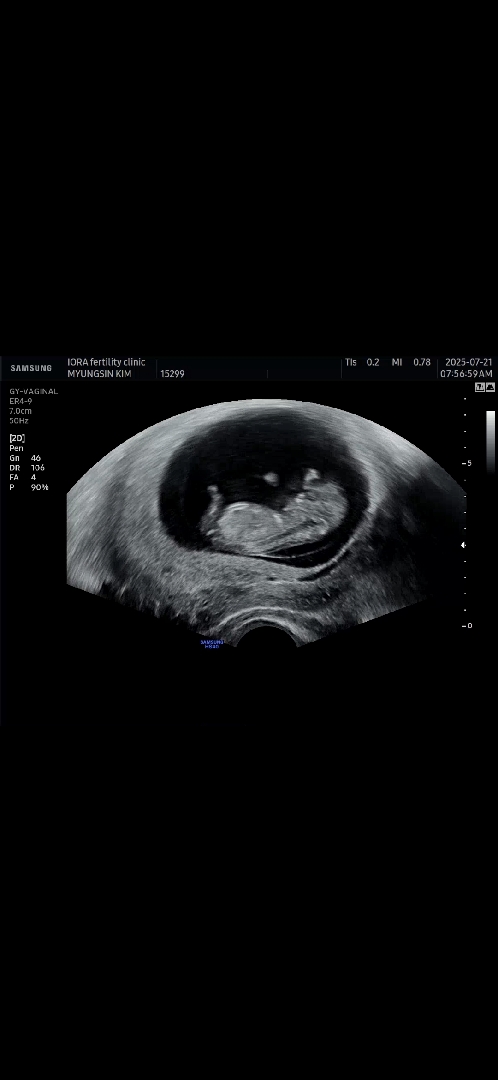

11주 각도법?

각도법 볼 수 있는 사진 맞을까요? 성별 예측해주세요~

아들같아용